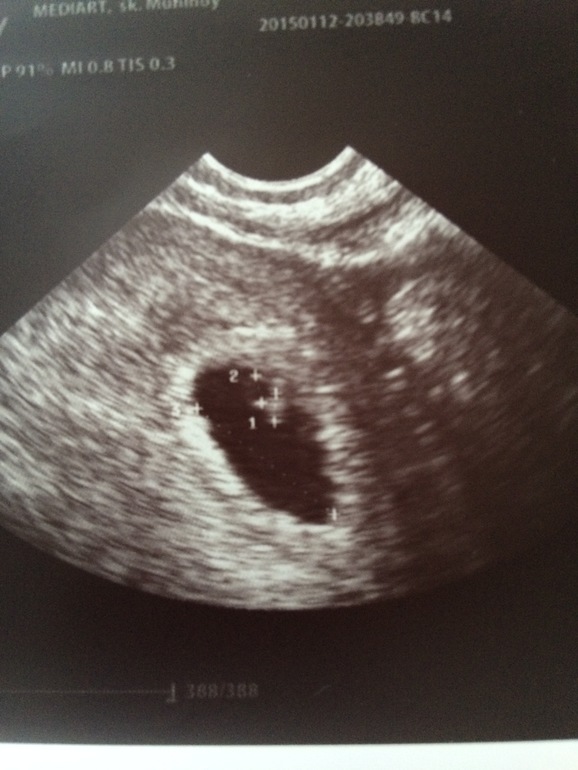

УЗИ на 6 недель и 1 день

УЗИ, КТГ, доплерВчера была на узи) Увидели и услышали нас) Сердечко бьется со скоростью 153 удара в минуту. Плод расположен по передней стенке матки и ттт у нас везде все хорошо!